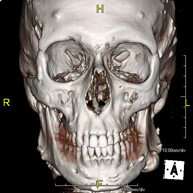

Prueba radiológica que consiste en obtener imágenes del macizo facial (cara) de alta definición anatómica mediante el empleo de un equipo de TC (Tomografía Computarizada). Indicaciones: tumores, cirugía plástica. - TC Oídos